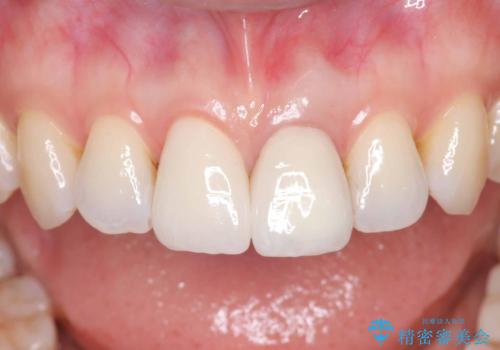

精密根管治療を行い、その後オールセラミッククラウンで審美的に修復しています。あわせてホワイトニングとエアフローによるクリーニングも行い、自然で美しい仕上がりとなりました。

他院で抜歯と診断された歯が、当院での治療により2本とも保存でき、見た目もきれいに仕上がりました。患者様にも大変ご満足いただけました。